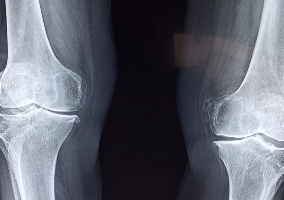

1. 관절 증상 개선

MSM은 관절의 염증을 줄이고, 연골의 파괴를 방지하며, 관절 윤활액의 분비를 촉진합니다. 이러한 작용으로 인해 관절염이나 퇴행성 관절염 등의 증상을 완화할 수 있습니다.